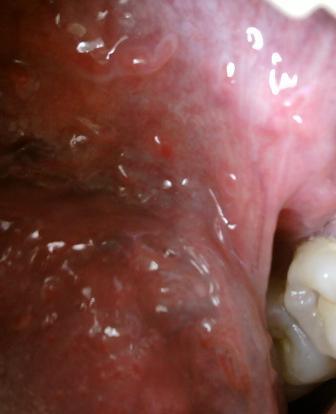

石家庄九州皮肤病医院 > 尖锐湿疣 > > > 口腔尖锐湿疣症状是怎样的口腔尖锐湿疣患者在患者 中占据的比例是比较小的。口腔尖锐湿疣一般是通过口交而感染上病毒而患病的。口腔尖锐湿疣一般发病在舌头周围,症状表现为淡红色的小丘疹,隆起,如乳头状或者是菜花状。不及时治疗危害是很大的。